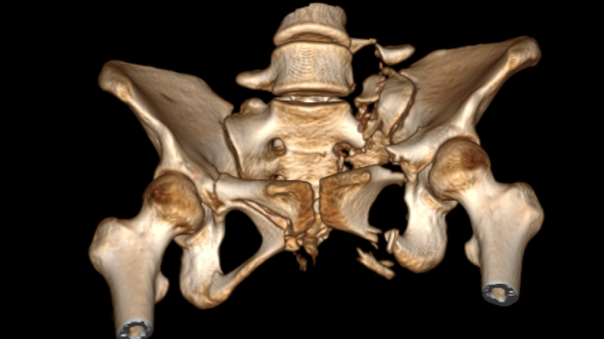

术前,手术团队进行了周密的准备,基于患者术前影像,借助基于AI与大数据的自动手术规划,将患者健侧肢体进行镜像配准,通过精细化自动分割与重建,实现个性化、定量化的复位规划。

图三:自动分割与重建

图四:人工智能复位规划